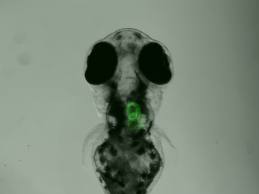

Un equipo de la Universidad Monash de Australia del Instituto de Medicina Regenerativa (ARMI), dirigido por el Dr. Yona Goldshmit y el profesor Peter Currie, descubrió el papel de una proteína en la notable capacidad de auto-sanación de los peces.

Los científicos descubrieron que la proteína, llamada factor de crecimiento de fibroblastos (FGF), controla la forma de la glía, y representó la diferencia en la respuesta a la lesión de la médula espinal entre los seres humanos y los peces cebra.

Los científicos demostraron que la proteína podría ser manipulado en el pez cebra para acelerar la reparación de los tejidos aún más.